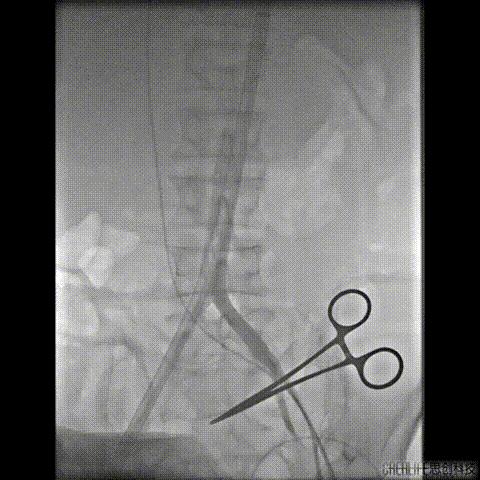

导丝跨瓣及测压

导丝跨瓣后测得跨瓣压差

升主动脉压104/36mmHg

左室压145/15mmHg

跨瓣压差41mmHg

此时患者出现室速 血气提示代谢性酸中毒、高钾血症,予电复率、补碱、补镁、碘氨酮等治疗后恢复窦性心律。